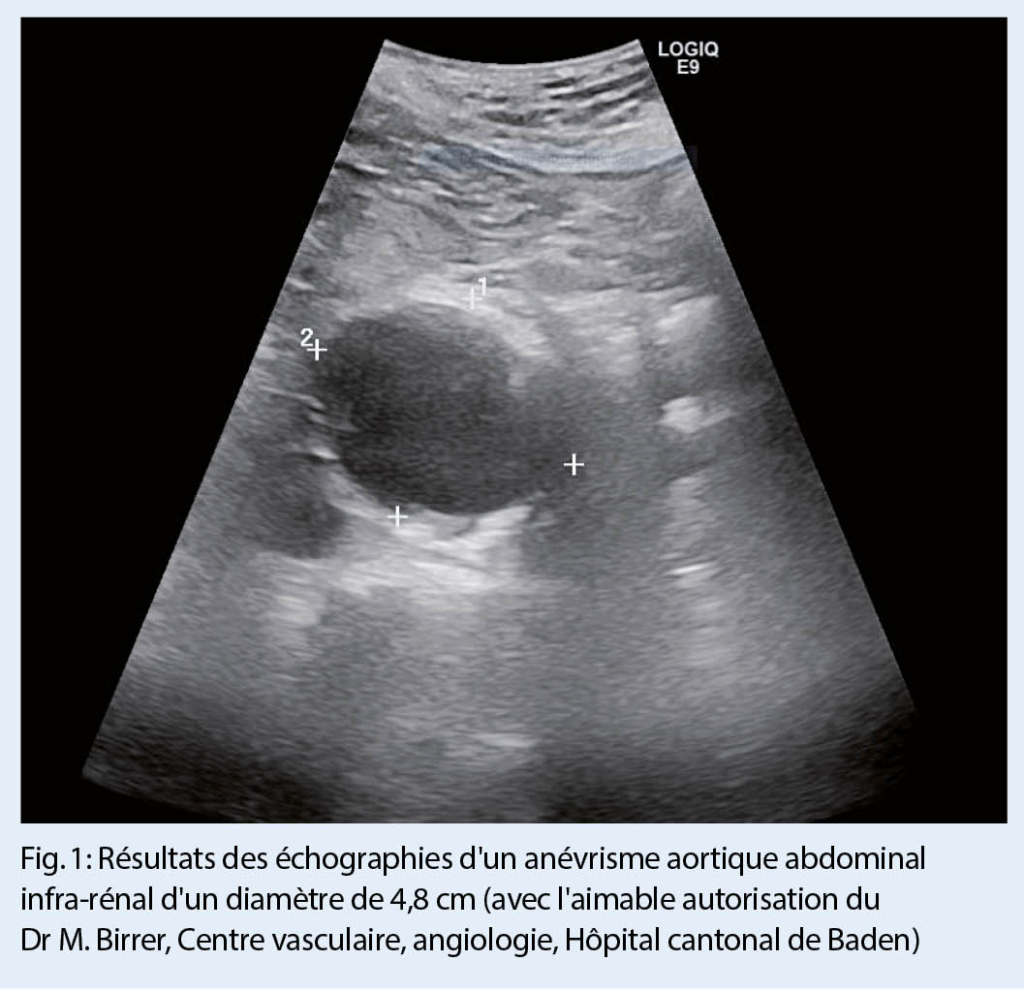

Il s’ avère que le dépistage pour l’ AAA remplit ces critères de manière idéale. Quatre grandes études randomisées ont déjà été consacrées à comprendre si le dépistage pour l’ AAA pouvait réduire la mortalité auprès du groupe cible (les hommes de plus de 65 ans) dans le cas d’ anévrisme (6-9). Deux de ces études ont été menées en Grande Bretagne, une au Danemark et une autre en Australie. Une seule de ces quatre études a été dédiée à la même question concernant les femmes (10). A chaque fois, la méthode de diagnostic utilisée a été l’ échographie, qui permet de poser un diagnostic exact dans 98.5 % des cas (fig. 1) (11).